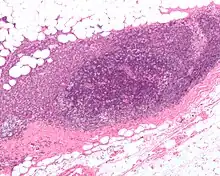

Micrograph showing a lymph node invaded by ductal breast carcinoma, with an extension of the tumor beyond the lymph node.